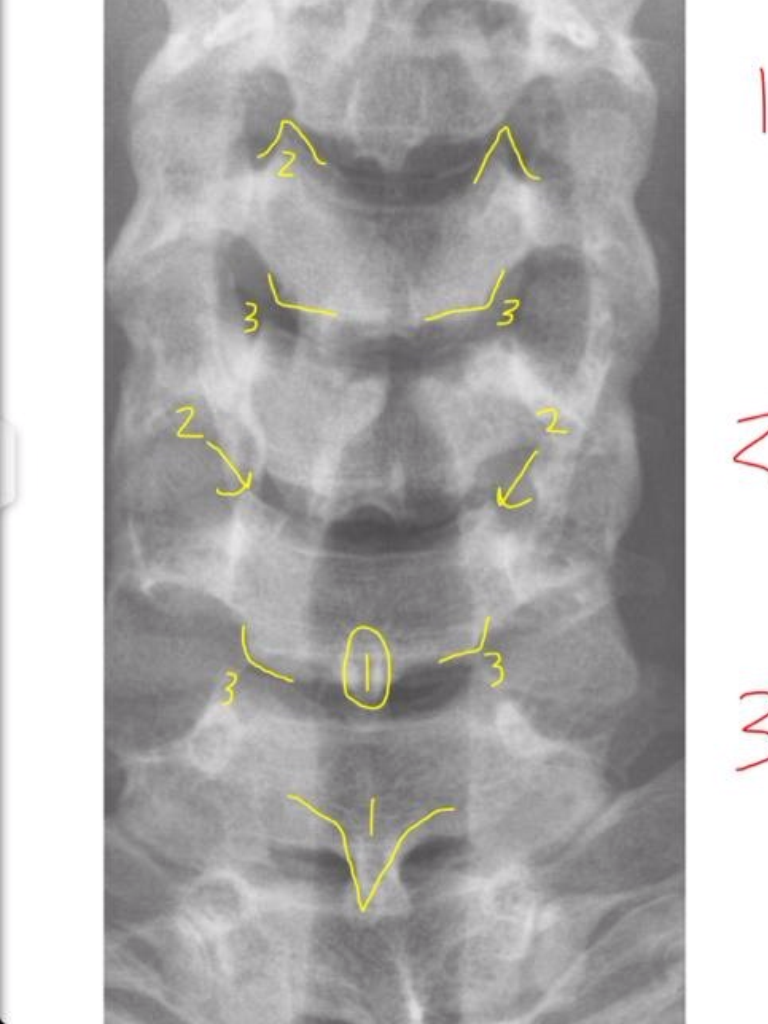

20

2

Pedicle Shadows

21

3

vertebral waist

(biconcave aspect of body)

22

4

Disc Spaces

(not disc itself)

23

5

Endplate Tips

(vertebral body)

24

1

Junction of Laminae

(tip of spinous)

Uncinate Processes

Inferior Aspects of Vertebral Bodies